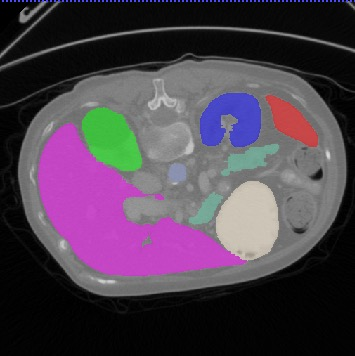

Transformers, the default model of choices in natural language processing, have drawn scant attention from the medical imaging community. Given the ability to exploit long-term dependencies, transformers are promising to help atypical convolutional neural networks (convnets) to overcome its inherent shortcomings of spatial inductive bias. However, most of recently proposed transformer-based segmentation approaches simply treated transformers as assisted modules to help encode global context into convolutional representations without investigating how to optimally combine self-attention (i.e., the core of transformers) with convolution. To address this issue, in this paper, we introduce nnFormer (i.e., Not-aNother transFormer), a powerful segmentation model with an interleaved architecture based on empirical combination of self-attention and convolution. In practice, nnFormer learns volumetric representations from 3D local volumes. Compared to the naive voxel-level self-attention implementation, such volume-based operations help to reduce the computational complexity by approximate 98% and 99.5% on Synapse and ACDC datasets, respectively. In comparison to prior-art network configurations, nnFormer achieves tremendous improvements over previous transformer-based methods on two commonly used datasets Synapse and ACDC. For instance, nnFormer outperforms Swin-UNet by over 7 percents on Synapse. Even when compared to nnUNet, currently the best performing fully-convolutional medical segmentation network, nnFormer still provides slightly better performance on Synapse and ACDC.